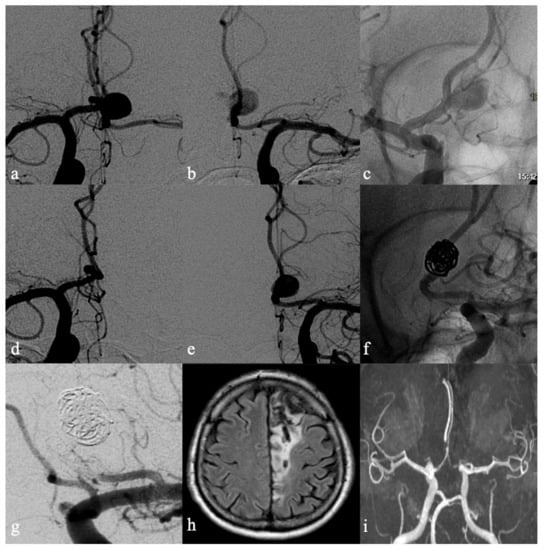

- Brinjikji, W.; Piano, M.; Fang, S.; Pero, G.; Kallmes, D.F.; Quilici, L.; Valvassori, L.; Lozupone, E.; Cloft, H.J.; Boccardi, E.; et al. Treatment of ruptured complex and large/giant ruptured cerebral aneurysms by acute coiling followed by staged flow diversion. J. Neurosurg. 2016, 125, 120–127. [Google Scholar] [CrossRef]